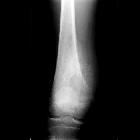

Aggressive periosteal reaction

Rapid irritative processes do not allow the periosteum time to lay down and consolidate new bone to form normal cortex. The cortex may appear lamellated, amorphous, or sunburst-like.

Aggressive periosteal reactions can not only be seen with malignant tumors, but also with more benign processes like infection, eosinophilic granuloma (Langerhans cell histiocytosis), aneurysmal bone cyst, osteoid osteoma, hemophilia , and trauma.